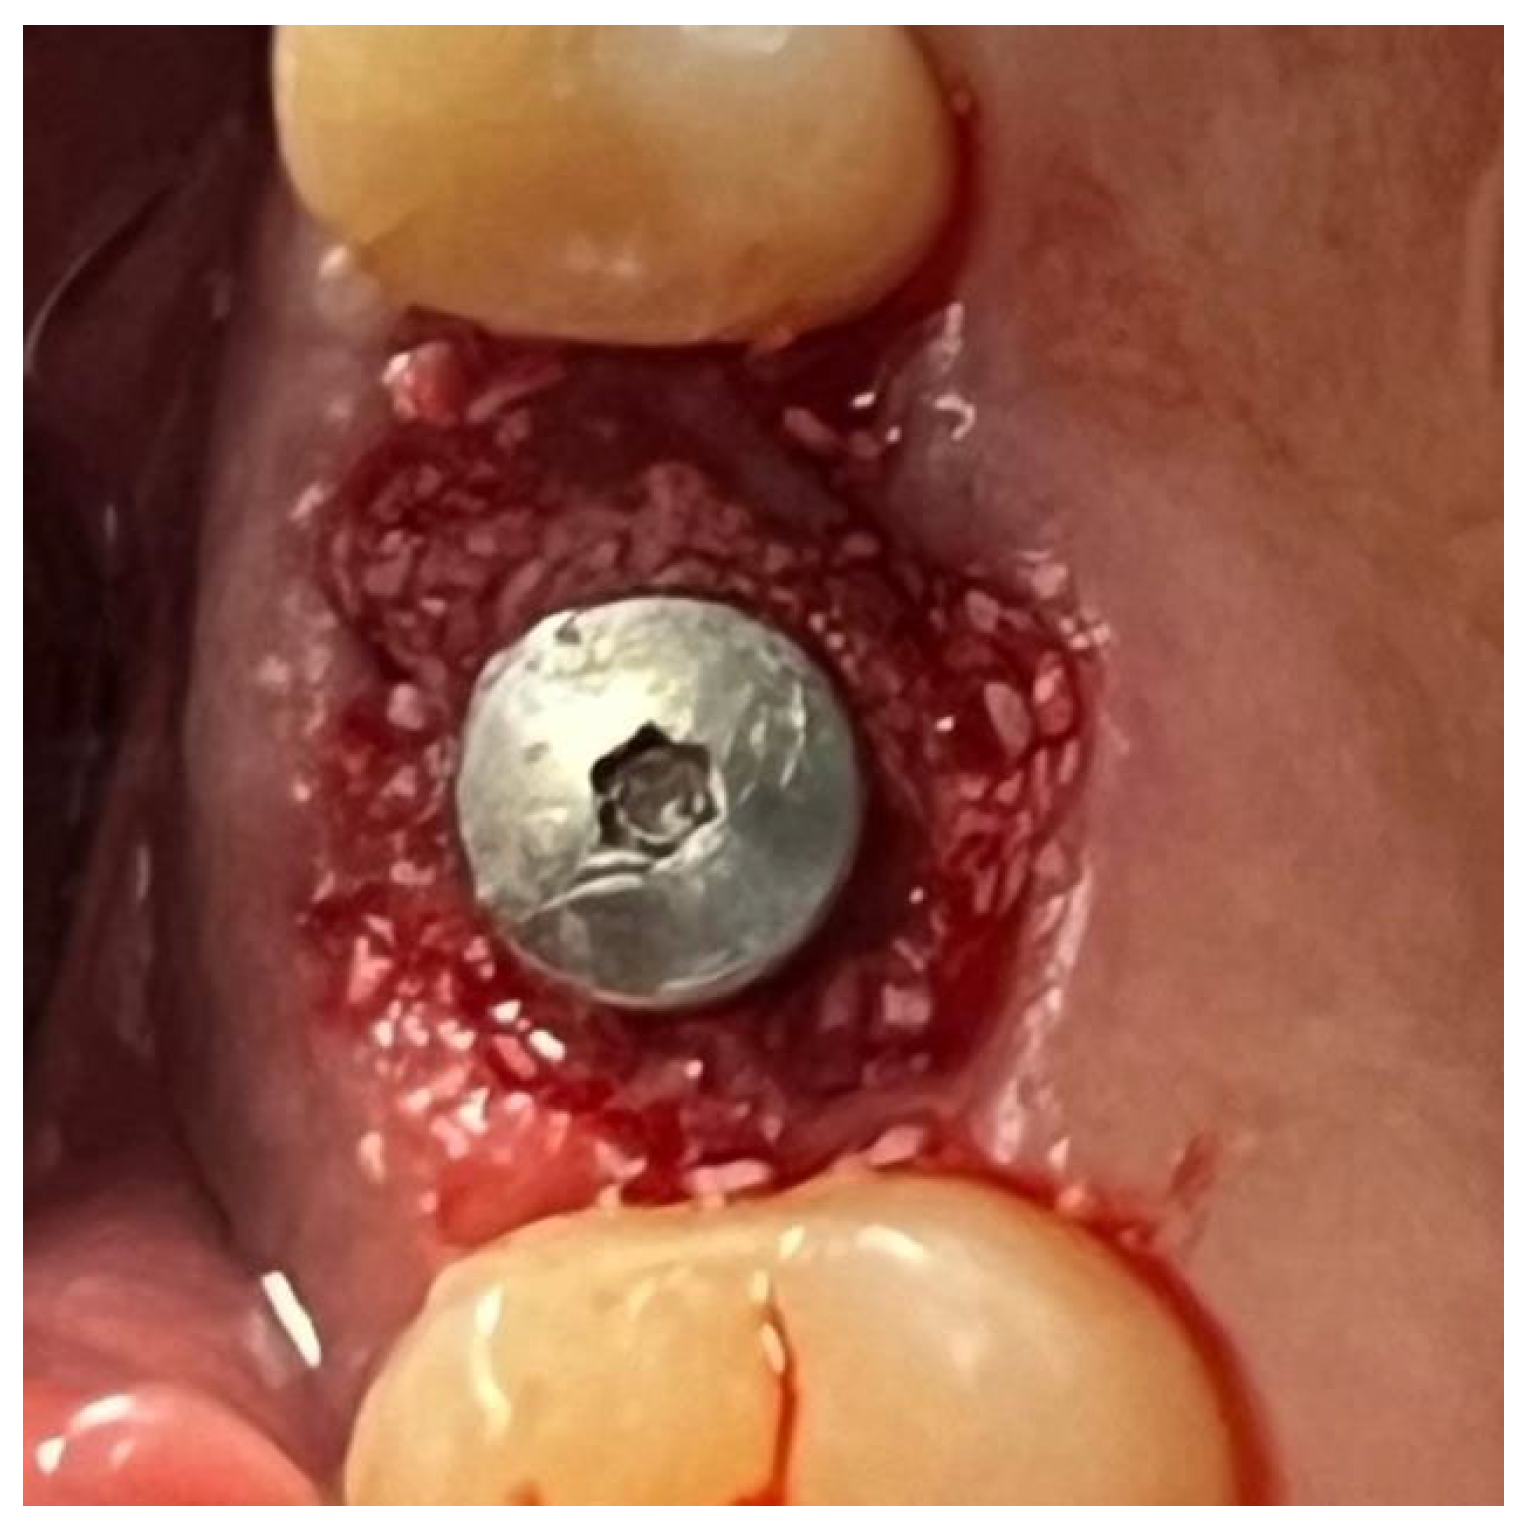

In a 49-year-old patient with ischemic heart disease, Glubran II was used as a stabilizing material for natural bone graft granules at a site rehabilitated with implant-prosthetic treatment, with the aim of achieving volumetric enhancement of the buccal bone. Following specific guidelines for surgical treatment of ischemic heart disease (4), implant therapy was carried out (Figure 8). Natural bone graft material (Bio-Oss®—Geistlich, Baden-Baden, Germany) was applied and stabilized with Glubran II. The application was made using an endodontic needle, depositing single droplets of the glue to cover the entire graft material before placing the prepared flap on top (Figure 9). This technique achieved stable graft fixation at the recipient site, demonstrating the efficacy of Glubran II for internal use (Figure 10).

Figure 10. Surgical site at the end of the polymerization time of Glubran II; the site was subjected to tensile testing, with positive results under the applied tensions.